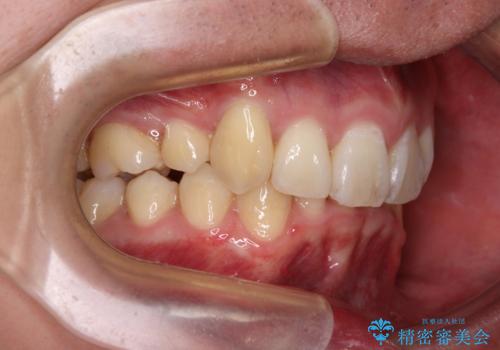

- 八重歯を気にして来院された患者様です。

顕著な上顎の八重歯とディープバイトであったため、上顎の左右第一小臼歯を抜歯することとしました。

犬歯歯根の位置や奥歯の咬み合わせから、ワイヤー装置での治療を強くおすすめいたしましたが、ご本人の強い希望により、妥協的な仕上がりとなることを了解いただき、インビザラインにて矯正治療を行うこととしました。

インビザライン単体で、左右ともに移動の難しい位置に歯根のある犬歯を整えるのは困難と判断し、補助装置を併用することとしました。

ディープバイトや奥歯の咬み合わせなど、インビザライン矯正では限界がありワイヤー装置での治療に及ばない仕上がりとなりました。

ただし、患者様としては八重歯や、それに伴う唇の閉じにくさが改善されたとのことで、納得いく状態での治療終了となりました。